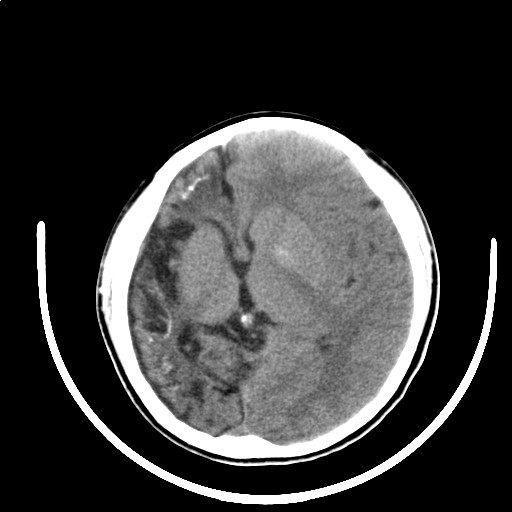

标题: PED3416:F,12Y,智力下降,学习成绩差,8个月时发过高烧。

右侧半球萎缩,软化,多量脑回样钙化,考虑颅面血管瘤病,建议dsa检查

右侧半球萎缩,软化,多量脑回样钙化,同侧颅盖板障增宽,考虑颅面血管瘤病,建议dsa检查与化脓性脑膜炎后遗改变鉴别。